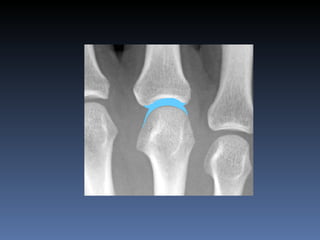

Osteoartritis IFDs, IFPs, 1 st  CMC Osteofitos Estrechez asimetrica del espacio articular  Esclerosis subcondral Quistes subcondrales No erosiones marginales Densidad osea preservada

Osteoartritis